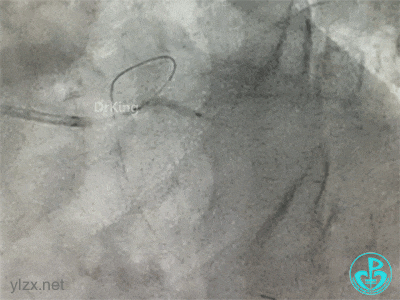

导丝Rewire回旋支,非顺应性球囊分别后扩张前降支和回旋支支架,对吻扩张。

患者术中血压偏低,一度出现烦躁。及时IABP置入是手术能顺利完成的保障。术前的准备很全面,造影结果如下。